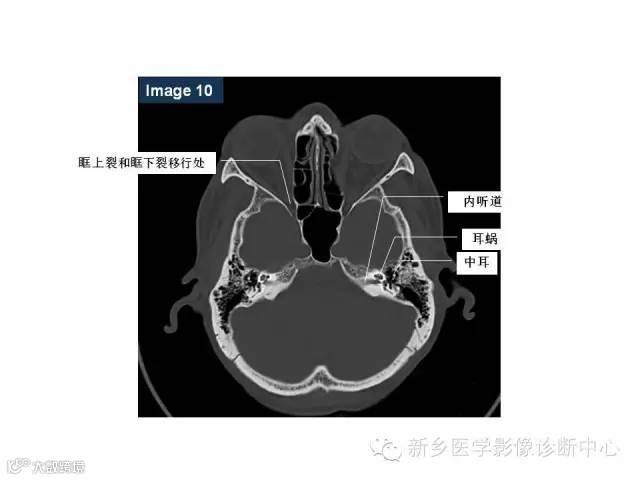

颅底孔道解剖详解

值得收藏!